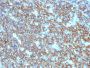

Positive Control

Daudi, Raji, and U266, and human lymphocytes. Lymph nodes and tonsils.

IHC, FFPE (verified)

IHC (FFPE) (verified)